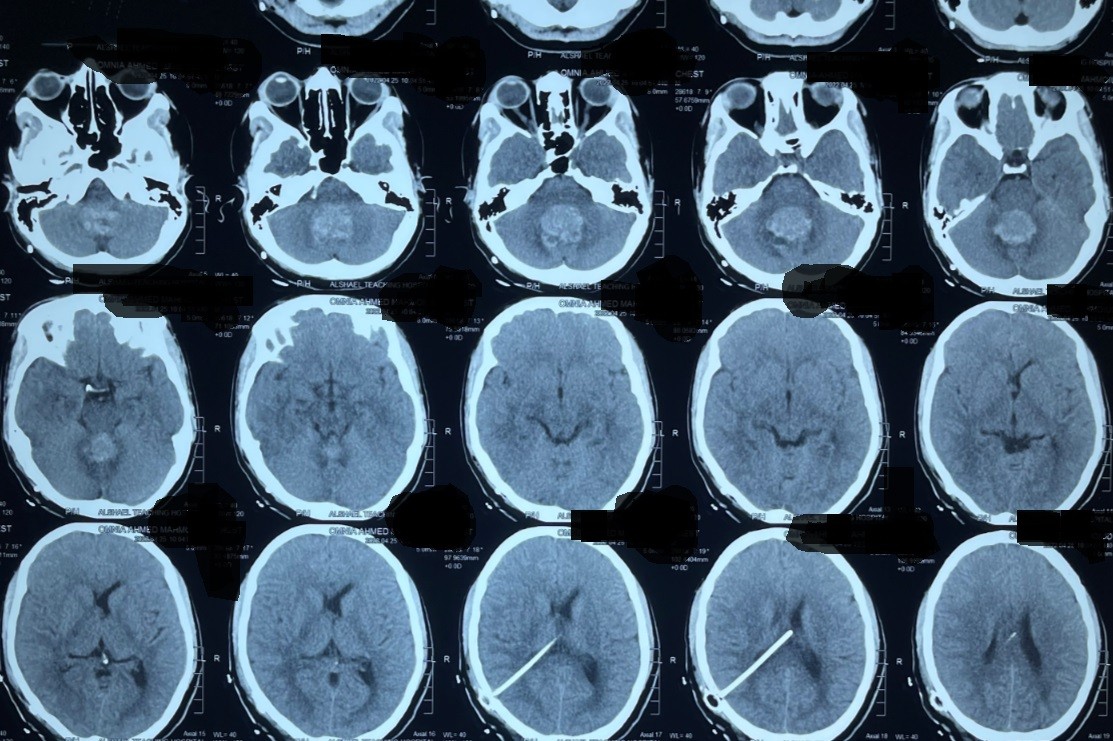

medulloblastomaورم بالحجرة الخلفية بالمخ

medulloblastoma A tumor in the posterior chamber of the brain

A successful precise surgery was performed to remove a tumor from the posterior cranial fossa, the area containing the cerebellum and brainstem. This region controls balance, motor coordination, and basic vital functions.